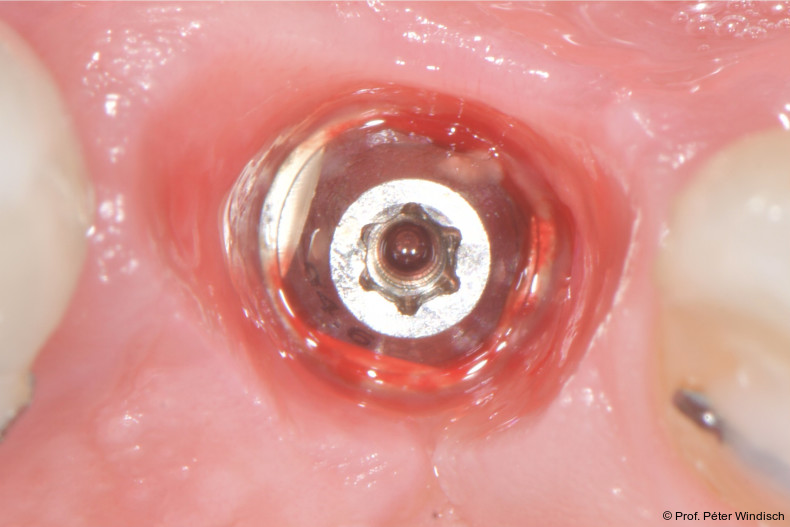

Nach einer Einwirkzeit von mindestens 60 Sekunden (Abb. 6) wurde die Tasche und die Implantatoberfläche gründlich mit Titanküretten instrumentiert. Während der Instrumentierung wurde das Reinigungsgel mehrmals in die Tasche appliziert und 60 Sekunden einwirken gelassen (ca. fünf bis sechs Mal), jeweils gefolgt von weiteren Instrumentierungszyklen. Dies wurde so oft wiederholt, bis keine sichtbaren Konkremente mehr aus der Tasche kamen (Abb. 7).

Nach Abschluss der submarginalen Instrumentierung wurde die Tasche mit Kochsalzlösung gespült und eine hochkonzentrierte, vernetzte Hyaluronsäure (xHyA, hyaDENT BG) in den Defekt appliziert (Abb. 8).